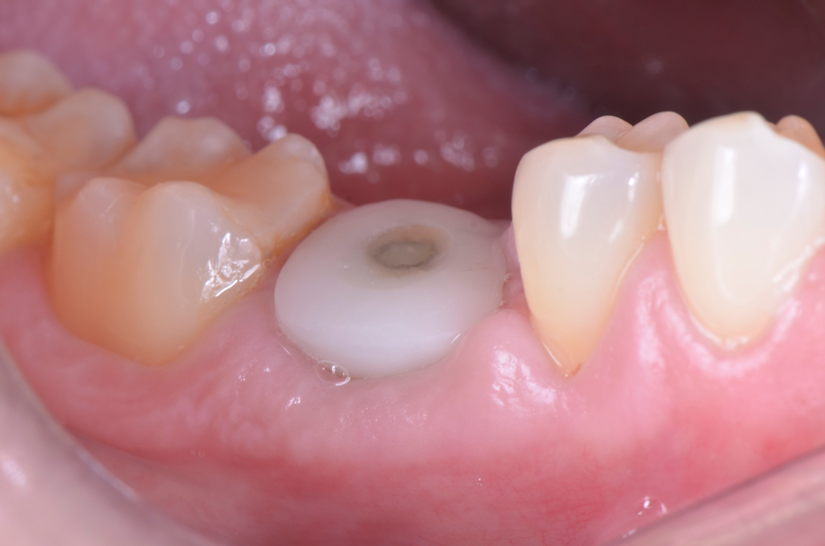

O paciente apresentou fratura vertical mésio-distal no elemento 46. Foi planejada a exodontia minimamente traumática e instalação imediata do implante Maestro Superiore (Implacil Osstem) utilizando uma guia prototipada. Após a exodontia, o implante foi instalado seguindo o protocolo de cirurgia guiada. O GAP vestibular foi preenchido com o Extra Graft. Um cicatrizador personalizado impresso com haletas facilitadoras foi capturado com resina flow e instalado. Após 30 dias, foi realizado escaneamento indireto para obtenção do perfil de emergência, utilizando protocolo digital com sobreposição do cicatrizador escaneado para confecção da coroa definitiva em zircônia policristalina estabilizada por ítria.

Escaneamento digital e reabilitação com coroa definitiva

Neste caso, a sobreposição digital entre o cicatrizador escaneado e o desenho da coroa possibilitou comparar perfis de emergência com excelente adaptação clínica, contribuindo para um resultado estético e funcional adequado.

A associação entre cirurgia guiada, biomateriais osteocondutores, componentes personalizados e fluxo digital completo permitiu uma reabilitação precisa, estética e minimamente invasiva do dente 46. O uso do cicatrizador impresso personalizado mostrou-se eficaz na preservação do perfil de emergência, otimizando a integração entre cirurgia e prótese. Essa abordagem representa uma tendência moderna na Implantodontia digital, com benefícios clínicos e biológicos evidentes para o paciente.